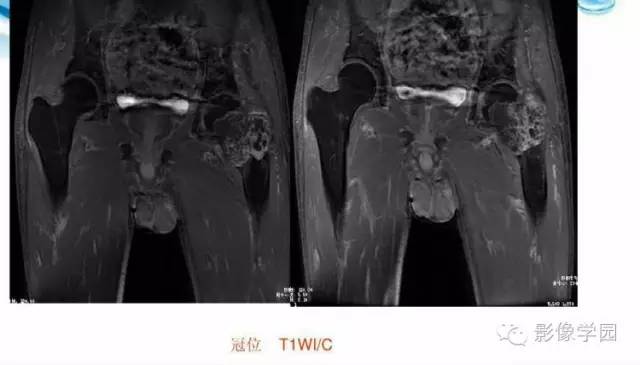

【病例】股骨软骨粘液样纤维瘤1例X线及MR影像表现